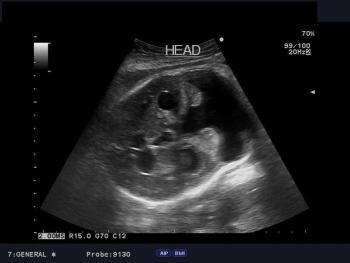

This is an early 3rd trimester pregnancy. What is your diagnosis of this placenta?

Identify the anomaly in this 35 week fetus as seen in these axial and sagittal images of fetal head.